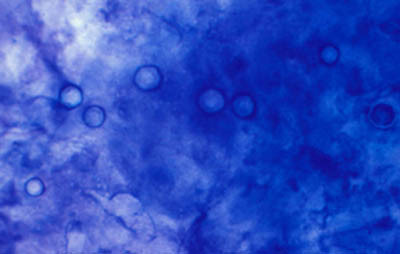

Microscopía Confocal

Frotis - extendido en capa

Preparaciones de extendido en capa sobre laminilla con agua destilada sin colorear, en campo claro y bajo contraste de fases: permite buena visualización de las formas Quísticas de Acanthamoeba

Magnificación 160x

- Microscopia Confocal : 94 a 100% de especificidad y 80 a 84% de sensibilidad